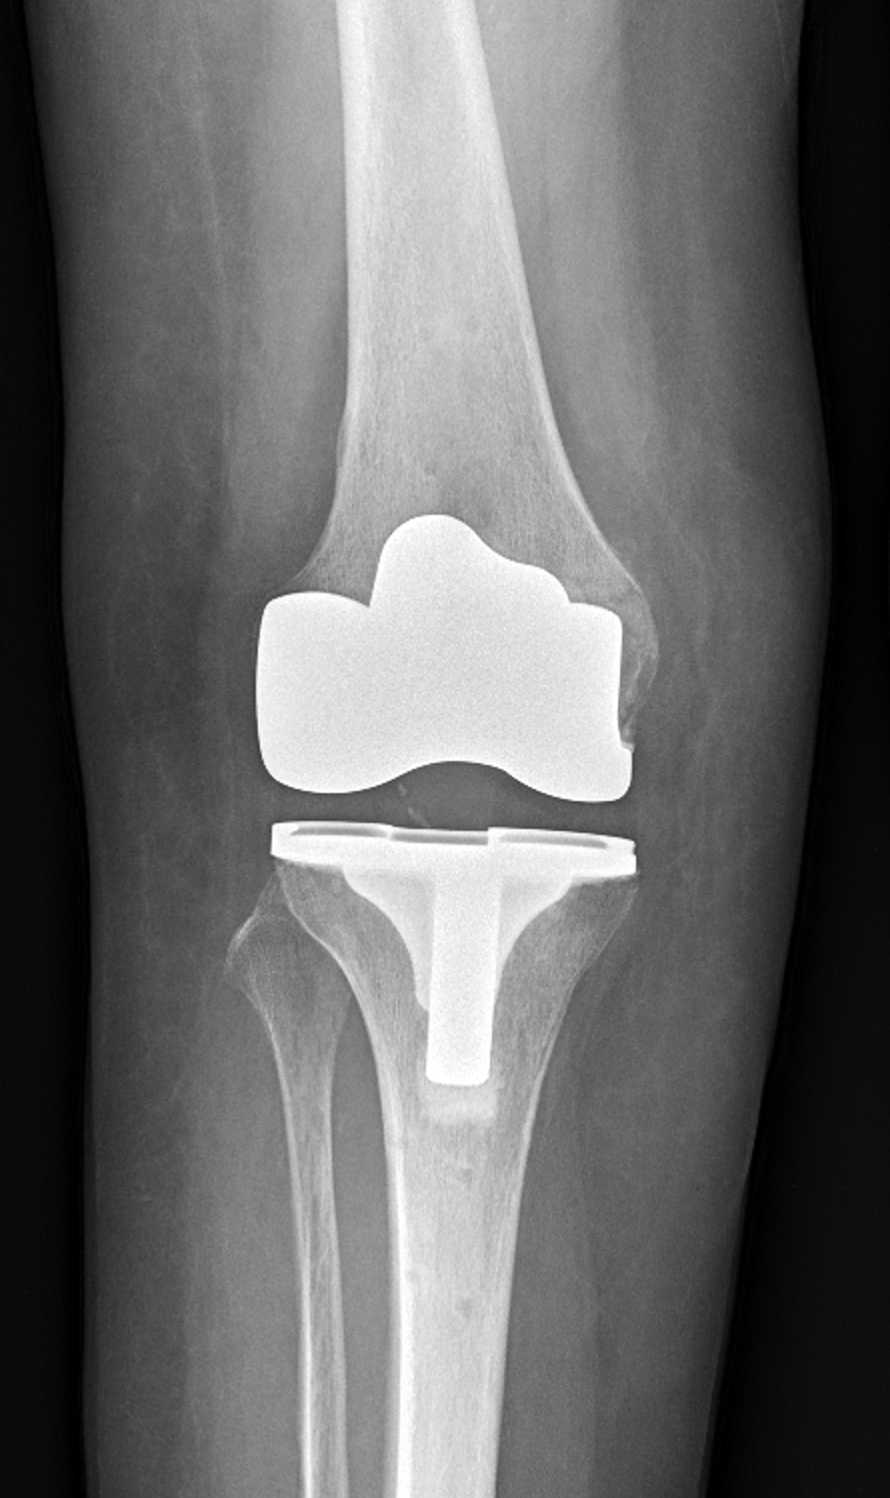

Endoprotéza je umělý kloub, který dokáže nahradit opotřebovaný či poškozený kloub člověka. Nejčastěji jde o kyčelní či kolenní kloub.

Náhrada kloubu je operace, při níž lékaři odstraní poškozené části kloubu a nahradí je speciálním implantátem – endoprotézou. Operace se provádí v celkové či spinální anestezii, případně v kombinaci s regionální svodnou anestezií.

Při postižení pouze části kloubu se provádí částečná náhrada (tzv. unikompartmentální náhrada, UNI).

U celkové náhrady (tzv. totální endoprotéza, TEP) jsou umělým kloubem nahrazeny všechny kloubní plochy.